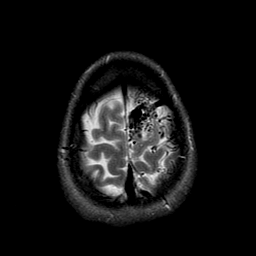

Vascular Malformation:T2-weighted MR #1 -- Slice #22

[Home][Help][Clinical] Slice 22